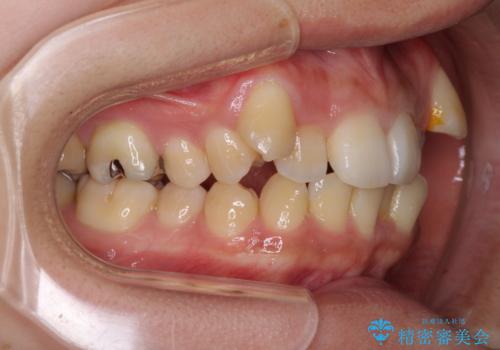

八重歯の抜歯矯正 補助装置を用いたインビザライン矯正

- 下の前歯のデコボコを気にして来院された患者様です。

来院当初、上顎の八重歯は気にしていらっしゃらなかったのですが、矯正治療をするのであれば、しっかりと治した方が良いと説明し、全顎矯正を行うこととしました。

八重歯の移動量が多く、インビザライン単体での治療は困難と判断し、補助装置により八重歯移動後にインビザラインを用いることとしました。